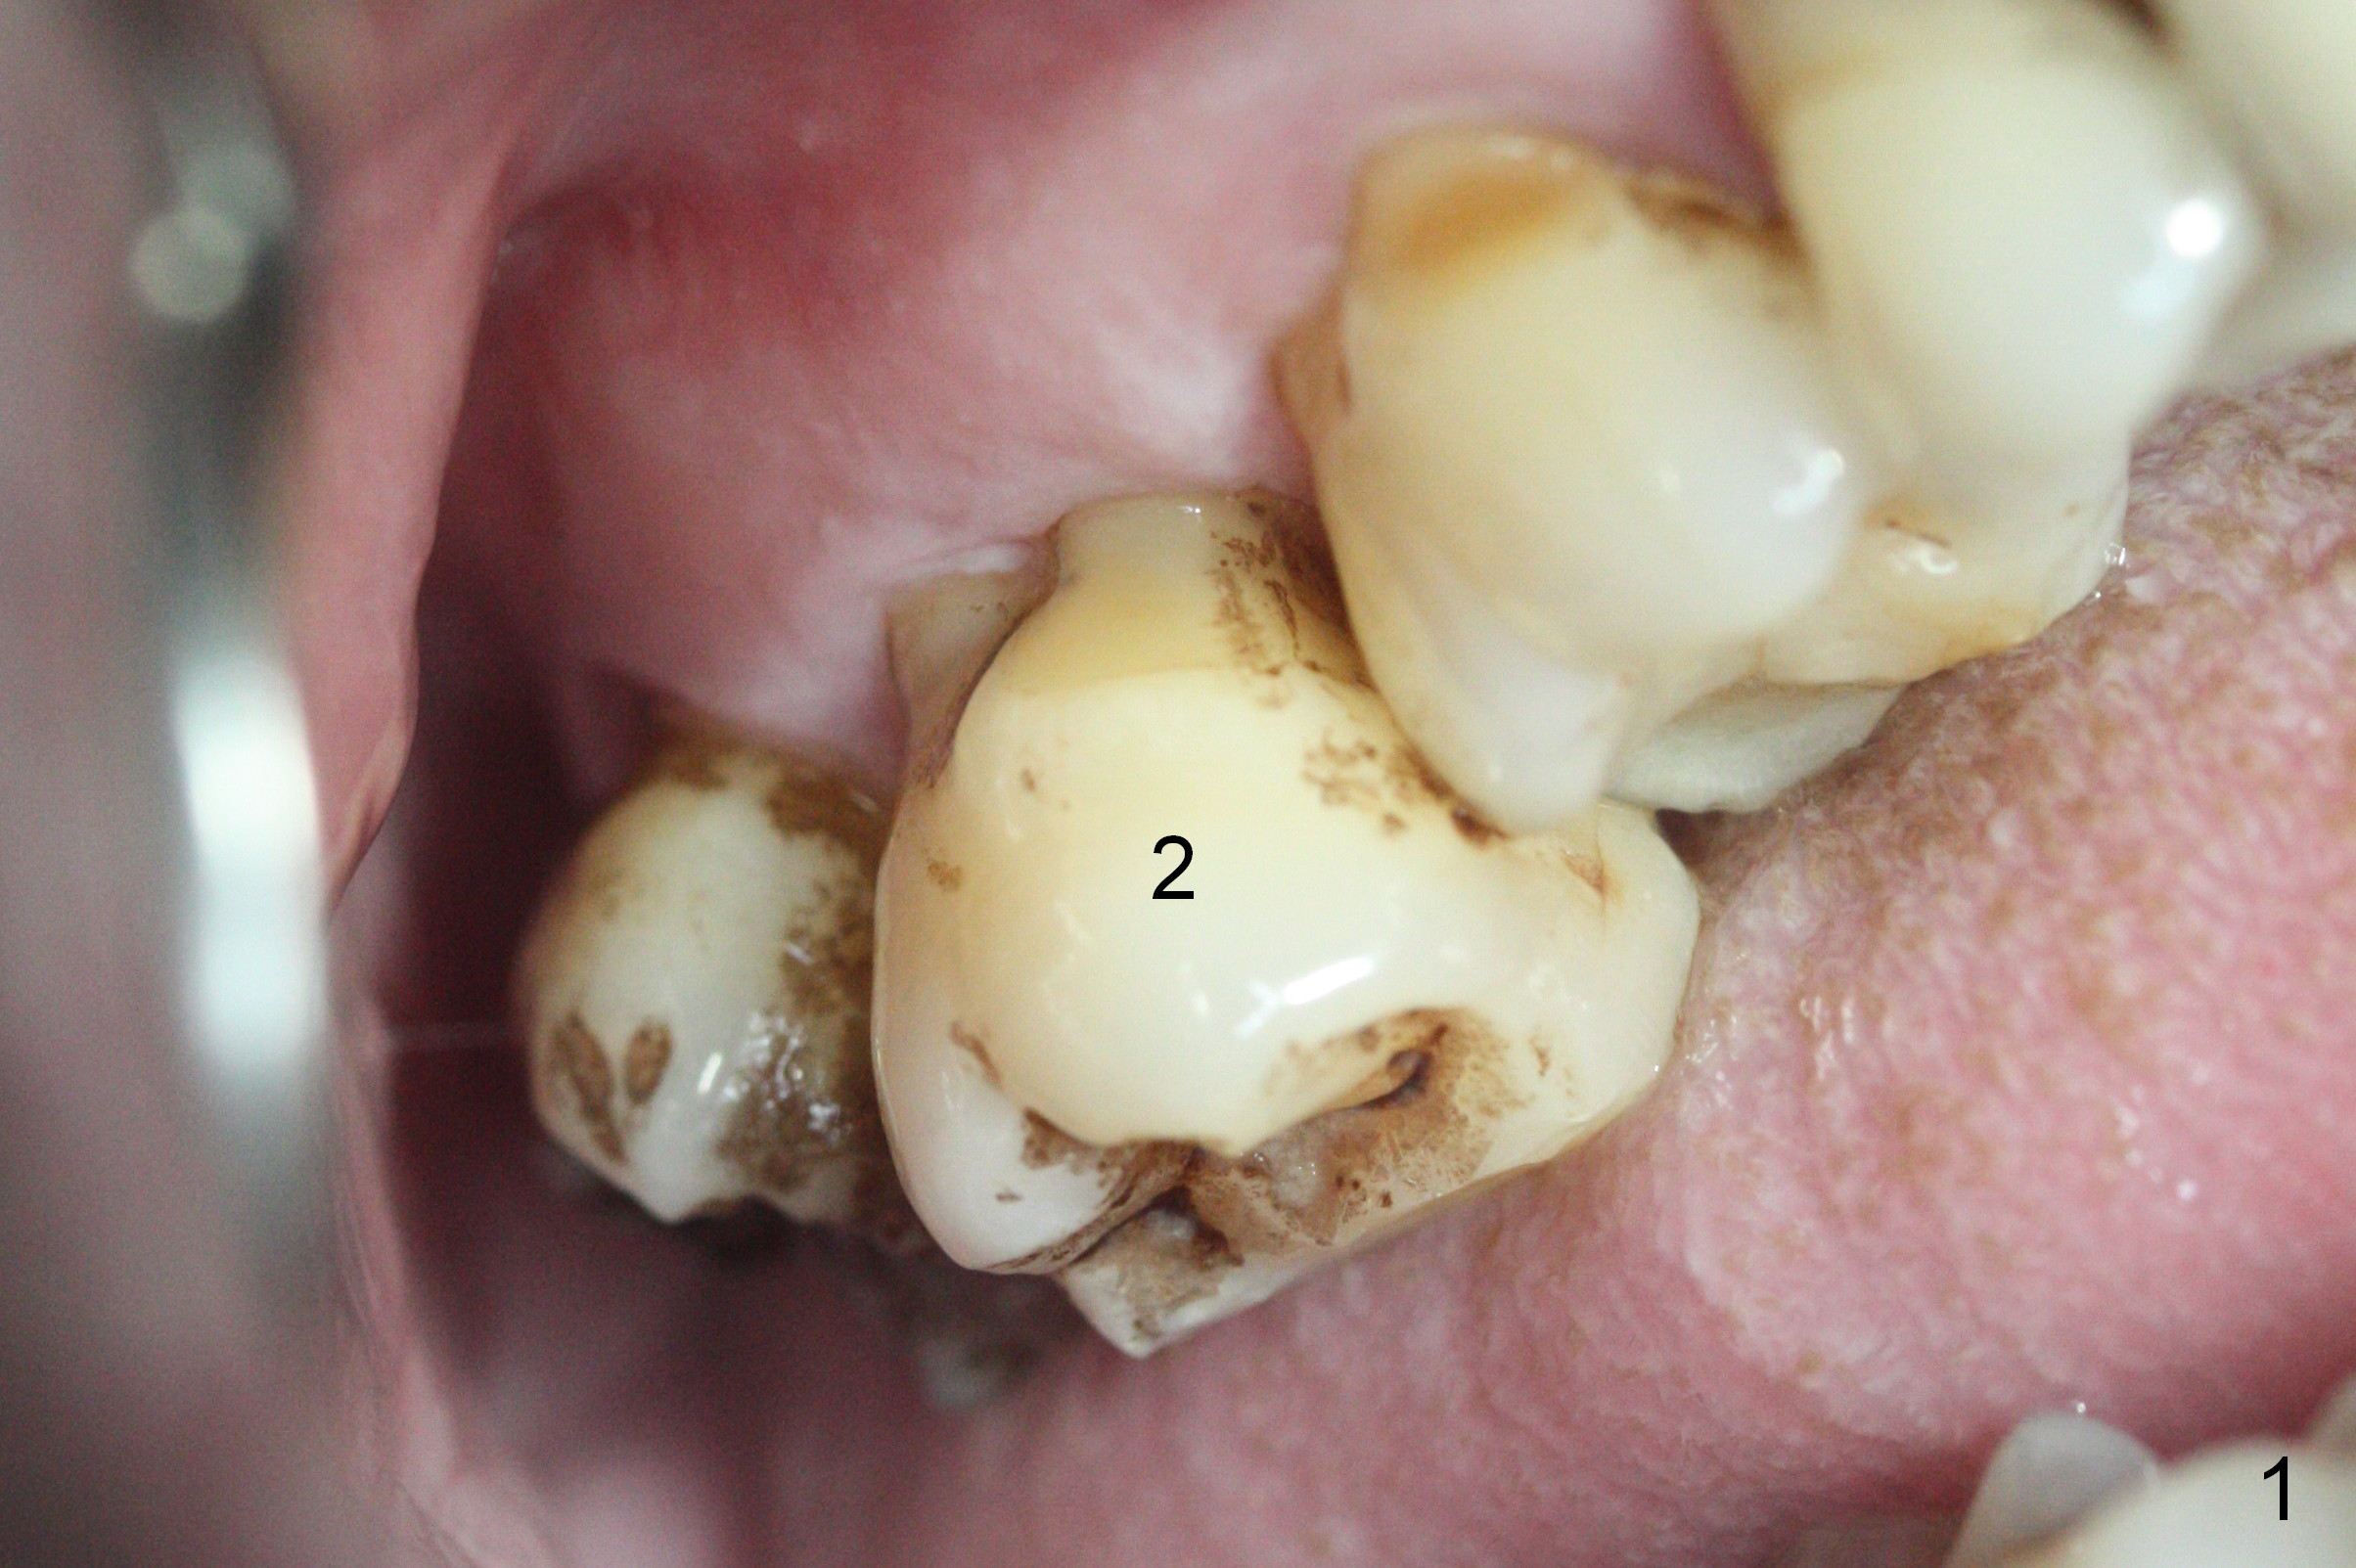

Two days post #31 implant placement, the patient returns for orthodontic intrusion of the tooth #2 with mini-implants (Fig.1). The palatal cusps have been trimmed (Fig.2 ^), since they almost contact a healing abutment at #31(*, Fig.3). Two mini-implants are to be placed mesiobuccal and distopalatal to the affected tooth. After minimal injection of Lidocaine, a 1.6x6 mm Tomas implant is placed in full length mesially (Fig.4), while the other (1.6x8 mm) half way (Fig.4). Following change in implant site mesially (Fig.6 >), the implant is half inserted (Fig.5). It appears that the tip of the distal implant is toward the tooth #1 (Fig.5). After withdrawing the implant partially, it is re-directed to apparently ideal trajectory (Fig.7). Ideally the mesial implant (Fig.8) should have been placed partially initially (Fig.4,5,7) so that the trajectory could have been able to be changed.

The buccal implant becomes loose in 2-3 months. When the wound heals (Fig.9 <), a 1.6x`10 mm implant is placed with the help of PAs for trajectory (Fig.10,11) and in the nonkeratinized gingiva (higher, the crestal bone may have been traumatized by previous implant placement, Fig.12). Two months later, the tooth #2 is partially intruded (Fig.13). A provisional (Fig.14 P) is fabricated in the osteointegrated implant at #31 with supraocclusion so that the remaining dentition has no occlusal contact (*). The periodontally compromised tooth #2 becomes in buccoversion in 2 months. The provisional is removed, while a lingual button is placed in the buccal surface of the tooth #2 (Fig.15). With power chain attached to the lingual mini-implant, the tooth #2 is lingualized in 2 months. The provisional and the implants are reused for final intrusion (Fig.16). The treatment is nearly 11 months. The buccal implant, although placed in the movable mucosa, remains stable and healthy (Fig.17). The tooth #1, as a guiding plane (to prevent #2 from distalization during intrusion), is not extracted after intrusion is completed.